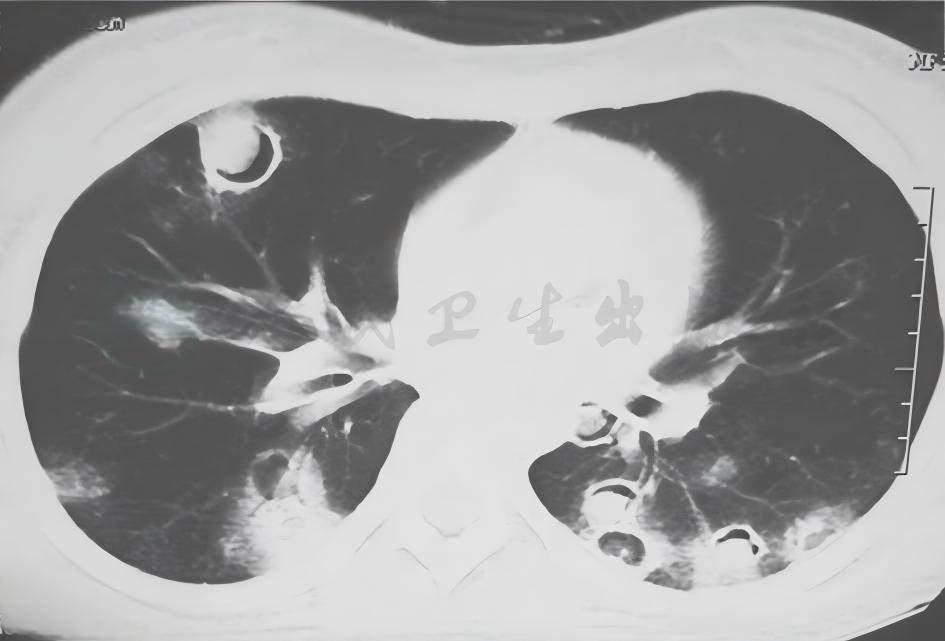

1小时条评论56岁女性,以间断咳嗽、咳痰1年,痰中带血半年入院。外院胸部CT提示双肺多发病灶伴空洞;外院病理报告慢性炎症,可见轻度核异质细胞。患者反复住院抗感染治疗无显效,复查胸部CT提示肺部病灶较前进展。未发现结核、真菌等病原学证据。如何诊治? 【病例简介】 患者...